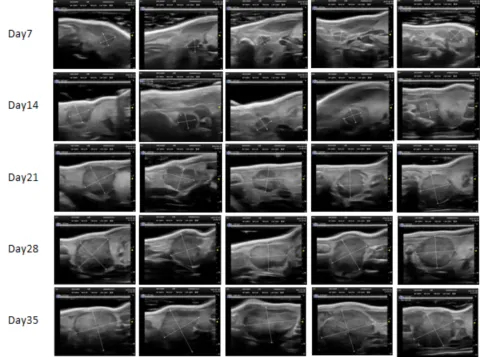

PDX Model (Growth Curve)

²¿·ÖÃÀ¸ß÷PDXÔλģ×Óչʾ